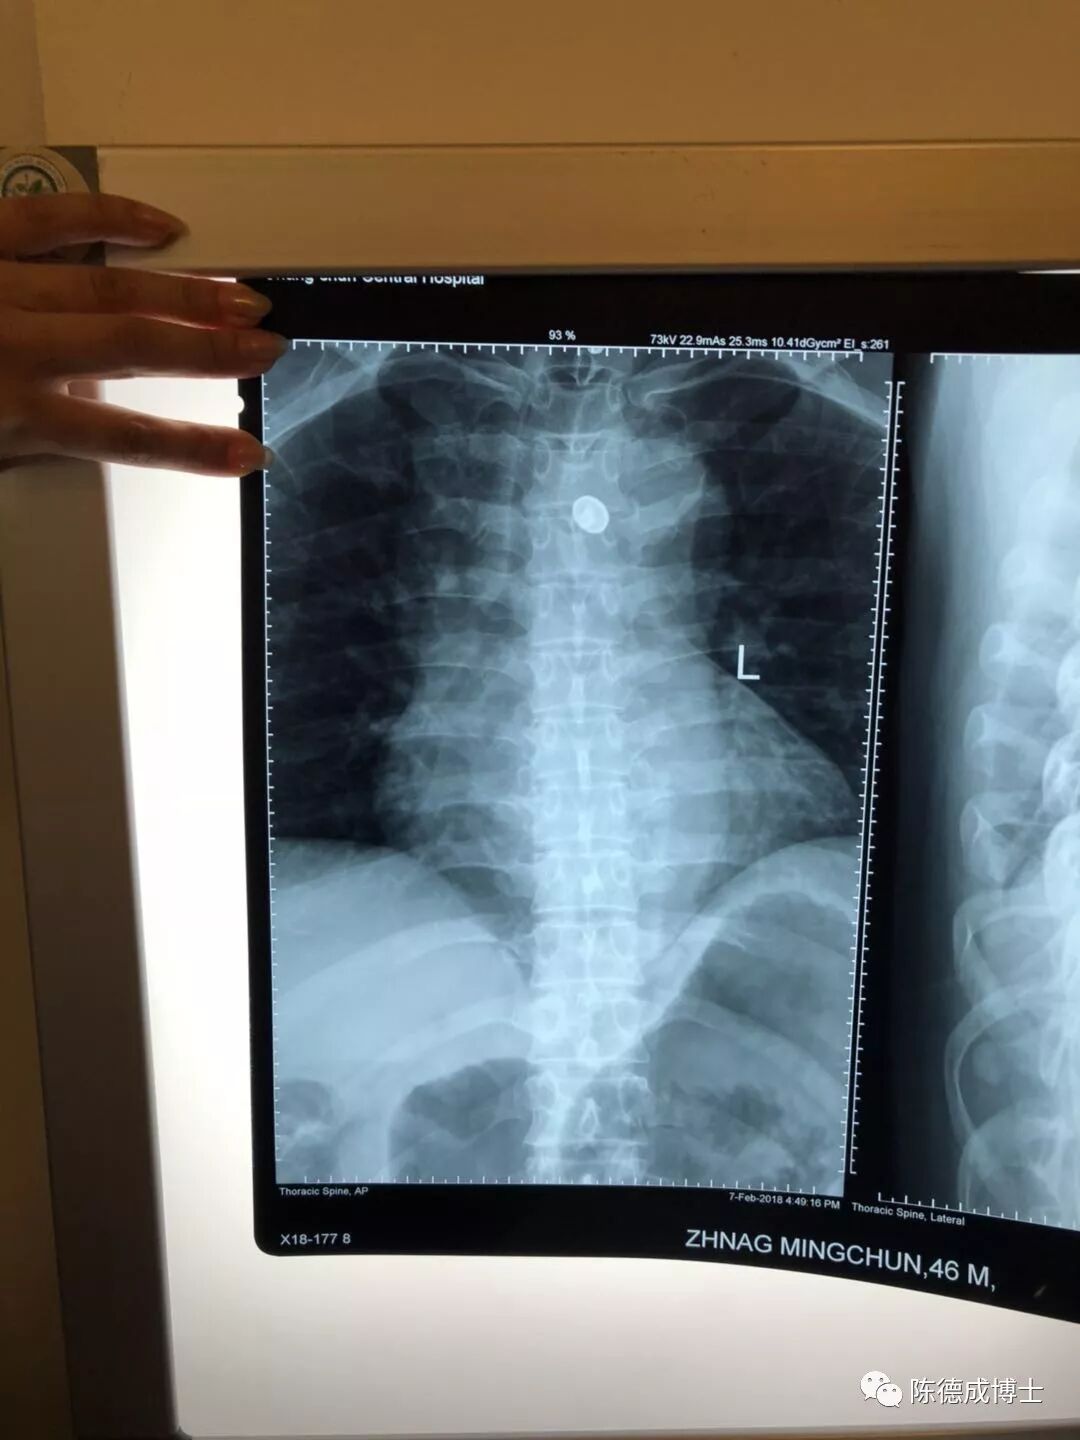

陈博士仔细看了我的胸椎X光片,又进行了触诊。耐心分析了我的病情。把脉、开方、针灸,并教了一套为我量身定制的运动保健操。